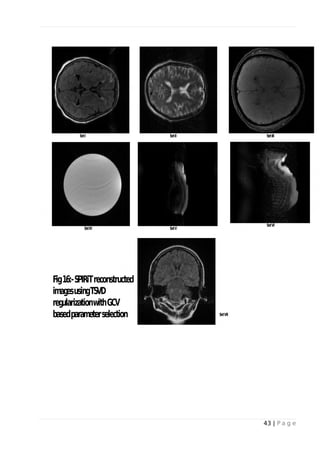

 GCV method for selecting truncation parameter in TSVD:

20 | P a g e

Fig-11 and Fig-15 shows the GCV values plotted as a function of the truncation parameter. The

optimum parameter is indicated using asterisk (*). It is evidently clear that optimum parameter

values are higher than L-curve. The reconstructed images are show in Fig-12 and Fig-16. Data set

V shows significant amount of aliasing and data set VI shows quiet amount of noise.

Fig 16: - SPIRiT reconstructed images using TSVD regularization with GCV based

parameter selection